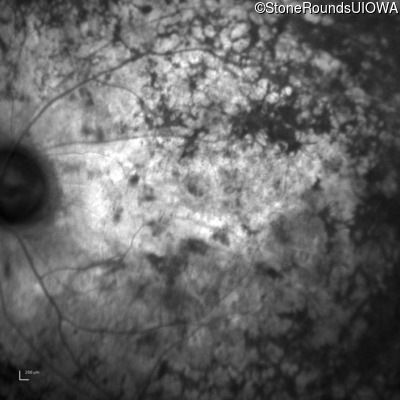

Infrared Fundus Photograph - Right - Light Perception

Exemplar

Infrared Fundus Photograph - Left - Light Perception